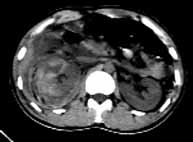

男性,22岁,车祸,被汽车方向盘压伤右季肋部,局部见长5cm的伤口。

ct表现:右侧肾上腺肿大,密度增高,右肾上极段肿胀,密度增高,右侧肾周间隙积血。

ct诊断:右肾及肾上腺挫裂伤